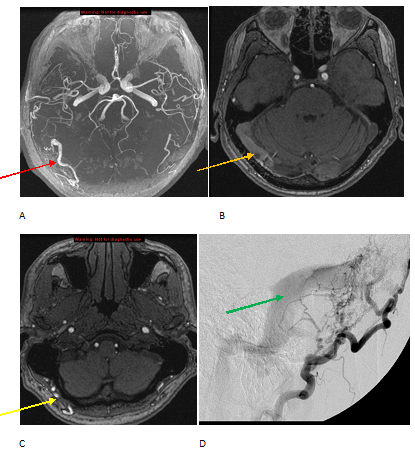

Figure 1: A-C maximum intensity projection (A) and source images (B-C) from an MR angiogram demonstrate enlargement of the right occipital artery (red arrow) with a tangle of interosseus vessels (yellow arrow) and early flow related enhancement in the transverse sinus (orange arrow) . The constellation of findings is most consistent with an arterio-venous fistula. Lateral projection (D) from a cerebral angiogram demonstrates enlargement of the occipital artery and early opacification of the transverse sinus (green arrow) consistent with an arterio-venous fistula. No tangle of vessels is seen to suggest an arterio-venous malformation.

In the evaluation of AVF’s, it is important to look for adjacent complications, especially parenchymal hemorrhage, venous infarcts and sinus thrombosis.

Morbidity of a dural AVF is primarily determined by the risk of hemorrhage and is graded using conventional angiography according to the Cognard classification. Dural AVF’s located in the sinus wall with no reflux and normal antegrade venous drainage have a low risk of hemorrhage; Those with extensive venous reflux and ectasia with involvement of the cortical veins have a hemorrhage risk near 65% and are treated, typically with embolization using a glue agent such as onyx (see figure 2). It is important to keep in mind that dural AVF’s can also occur within the spine where they present with variable but progressive myelopathy.